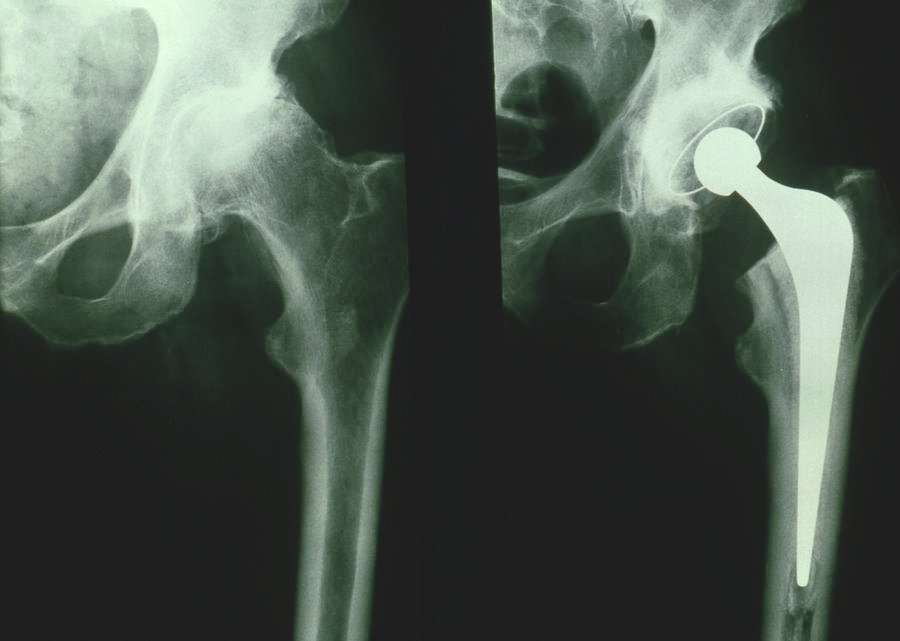

In this surgery, our surgeon surgically removes a damaged bone and cartilage caused by arthritis and replaces it with a metal or plastic prosthesis as an artificial joint. This hip replacement operation can treat patients with hip pain and make walking simpler for them.

Hip replacement can also be performed using a minimally invasive approach with a small incision. Our orthopaedic surgeon will use either general anaesthetic or a spinal block to numb the lower part of the body during the surgery. In India, we have approximately 20 years of experience in Hip Replacement Surgery and Revision Hip Replacement Surgery.

The surgery procedures vary from patient to patient based on their problem. In this surgery, our surgeon surgically removes a damaged bone and cartilage caused by arthritis and replaces it with a metal or plastic prosthesis as an artificial joint. This hip replacement operation can treat patients with hip pain and make walking simpler for them.